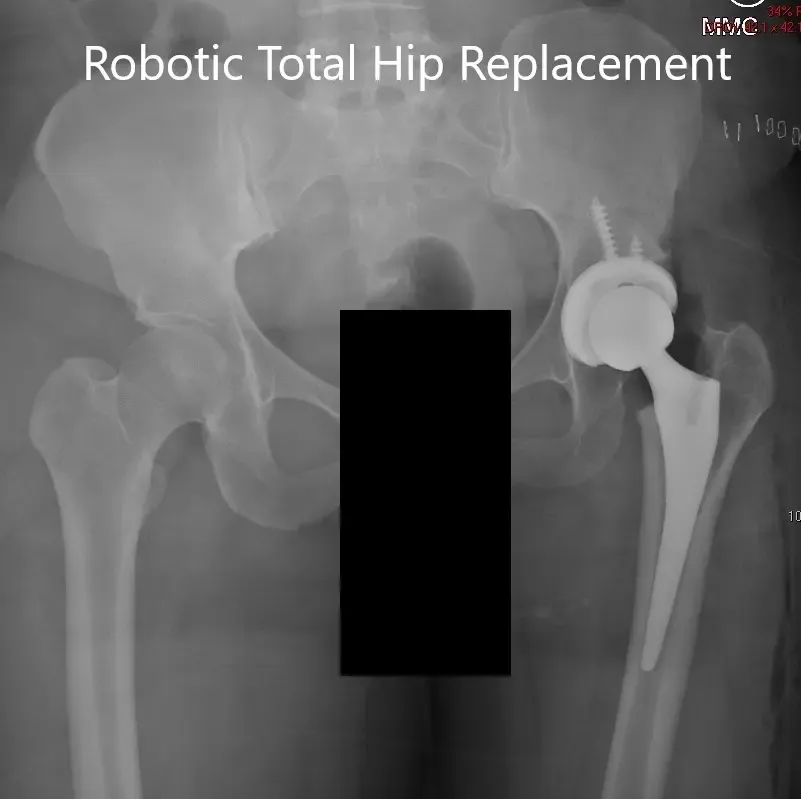

Tras realizarse el procedimiento, se realizó una radiografía y se visualizó la prótesis en la posición correcta.

Radiografía postoperatoria de la pelvis con ambas articulaciones de la cadera en la vista AP